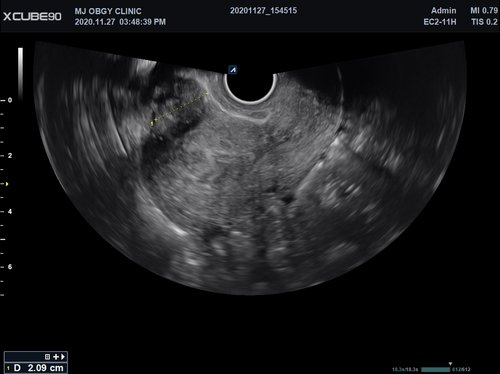

• EC2-11H (2-11 MHz) für Ultraschalluntersuchungen in Bereichen Geburtshilfe,

• Gynäkologie, Urologie, EM